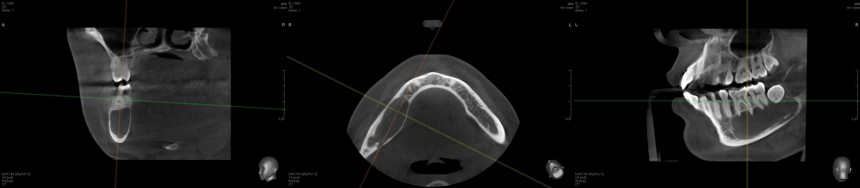

Примерно полтора года назад к нам в клинику обратилась молодая и красивая девушка. Все бы ничего, ничто ее не беспокоило, но вот однажды пошла она лечить зубки, и ей сделали панорамный снимок. Сделали панорамный снимок — забегали, заохали, послали на компьютерную томографию. Вот она:

или вот:

Для тех, кто не разбирается в компьютерной томографии, я поясняю:

Как видите, большую часть тела и ветви нижней челюсти справа занимает гигантская фолликулярная киста. Она образовалась из-за ретинированного зуба мудрости #48. Дело в том, что вокруг ретинированных зубов мудрости сохраняется фолликул, оболочка зачатка зуба. И в определенных условиях (каких — науке пока неизвестно) клетки фолликула могут пойти в рост — он постепенно вытесняет костную ткань и формирует гигантские кисты, которые называются фолликулярными.

- Полость кисты очень большая, переходит с тела на ветвь нижней челюсти. Проблема решаема правильным доступом.

- Где-то на дне полости кисты находится нижнелуночковый нерв (на картинке ниже выделен красным). У пациентки пока нет парестезии, это дает основания предполагать, что нервный ствол не поврежден и располагается за пределами полости кисты. Нужно соблюдать осторожность и, на всякий случай, предупредить пациентку о возможном возникновении парестезии после операции.

- Из-за больших объемов полости, у тела и ветви нижней челюсти остались очень тонкие костные стенки. И, даже если мы удалим кисту через относительно небольшой доступ, мы этим самым доступом ослабим и без того невысокую прочность нижней челюсти. Может случиться перелом даже во время зевка. Поэтому следует подумать о каком-то армировании или укреплении раны после операции. Запасаемся титановыми минипластинами и винтами.

- 46 и 47 зубы проникают в полость кисты, электроодонтодиагностика показывает высокие значения (некроз пульпы). Следовательно, если оставить эти зубки с пульпой, останется риск рецидива кисты уже из-за этих зубов. Их нужно депульпировать — и это главная предоперационная подготовка их депульпированием занимается врач-терапевт.

- Из опыта предыдущих операций я знаю, что нередко оболочка кисты образует спайки с корнями зубов, поэтому очень сложно от них отделяется. Нужно быть готовым на расширение доступа и резекцию верхушек корней 46 и 47 зубов.